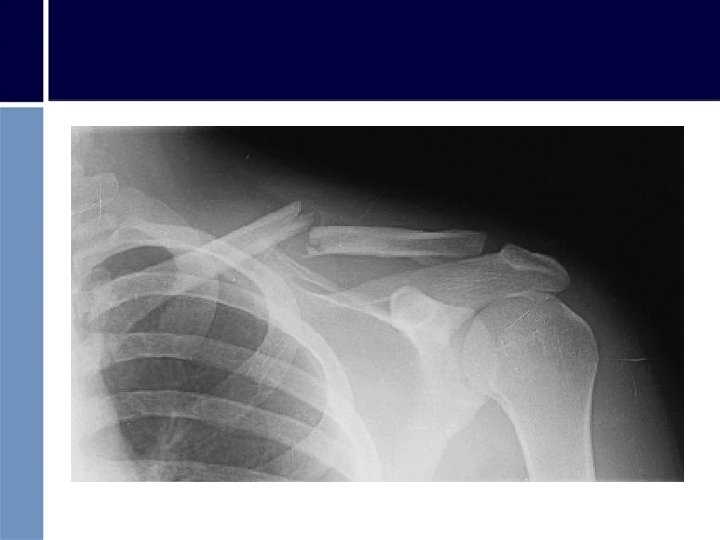

FRACTURA DE CLAVÍCULA Clavícula Fractura clavícula

FRACTURA DE CLAVÍCULA • Colocar brazo sobre el pecho con mano hacia hombro contrario a la lesión • Colocar vendaje Cabestrillo usando: – pañuelo, camisa, cinturón, corbata, etc.

FRACTURA BRAZO

FRACTURA DE BRAZO • Se colocarán 2 férulas: una desde el hombro al codo y otra desde la axila hasta el antebrazo, se sujetarán con vendas. • Codo en 90º y muñeca en extensión • Proteger axila con algodón o tela • Sostener brazo con cabestrillo • Trasladar a C. Asistencial